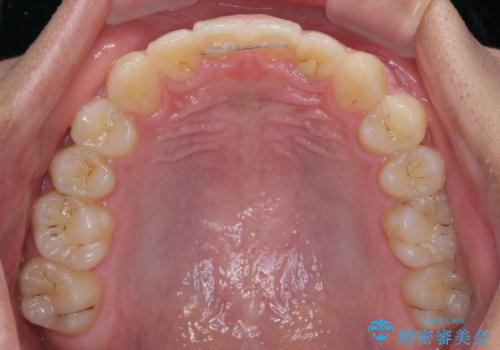

突き上げによる隙間を予防する為に、深い咬み合わせを改善するような治療計画としました。咬み合わせを改善させることはできましたが、隙間は後戻りしやすいので、通常の下顎前歯のみではなく、上顎前歯2本もワイヤーで保定を行いました。

高校生ということで、非常に短期間で治療を終えることができました。